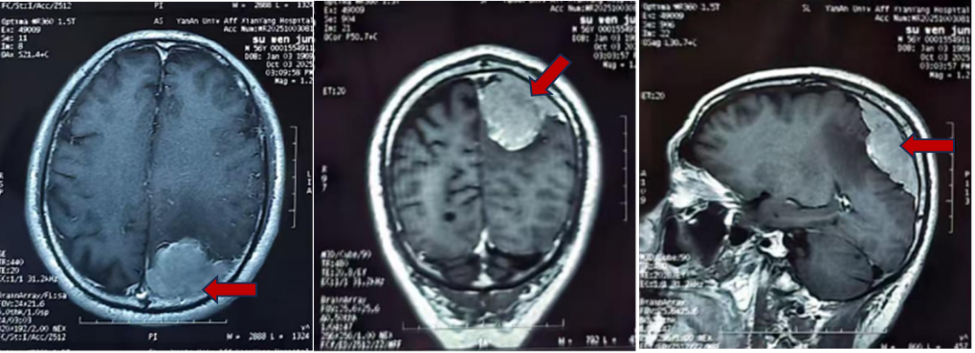

半年前,56岁的苏先生开始出现右手无力,每次发作约一天后自行缓解,无头痛头晕等不适,他便未予重视。直到数月后,同样的症状再次袭来,且右手活动明显受限,他这才意识到不对劲,立即赶往当地医院就诊。头颅磁共振检查的结果令人心惊——他的左侧头颅顶部有一个约6*8cm的巨大占位,近乎成年人的拳头大小,医生初步判断为脑膜瘤。

辗转多家医院后,苏先生带着最后的希望,来到二一五医院神经外科。入院后进一步检查发现,这颗“拳头”已经压迫并侵袭了脑部重要的静脉血管——上矢状窦。神经外科千超主任医师、张毓主任医师及李海马博士团队迅速评估后指出,若不及时手术,肿瘤及周围水肿面积会继续扩大,最终将导致右侧肢体永久性偏瘫。开颅肿瘤切除术,是解除压迫、根治疾病的唯一选择!